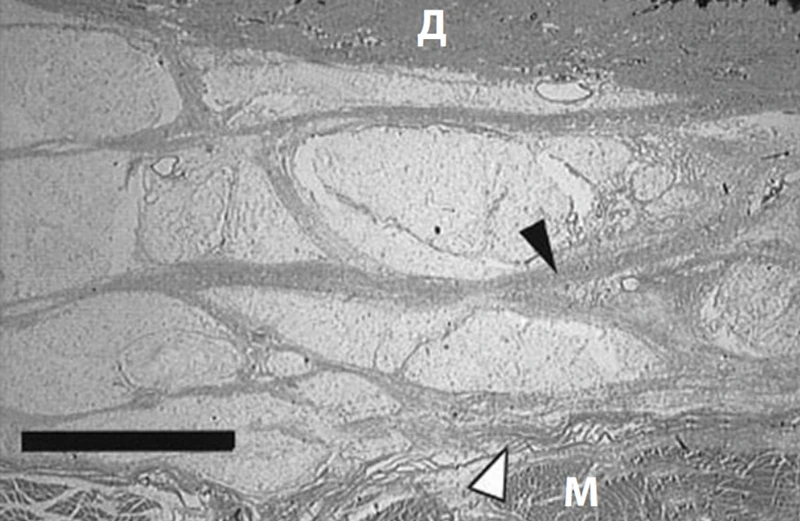

• жировой слой и дерма (образуют фибросептальную сеть, которая разделяет жировую ткань на дольки и затем крепится к дерме, формируя связки кожи retinaculum cutis; RC). RC защищают кожу от гравитации и растяжения, а также сохраняют трехмерную волокнистую структуру (рис. 2)3. С возрастом происходит уменьшение площади и толщины RC, параллельно усугубляется дряблость кожи (рис. 3, 4)4, 5.

Рис. 2. Кожные связки (retinaculum cutis; RC) / фибросептальная сеть жировой ткани (ФСС) передней поверхности предплечья. Белые стрелки – глубокая фасция, черные – RC. М – мышца; Д – дерма3.